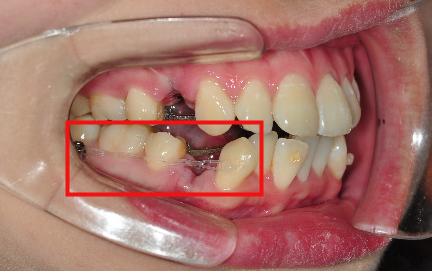

그리고 나서 하악 송곳니에 동그란 가짜치아(?) 를 만들어 주셧어요

이것과 스크류를 고무줄로 연결해서 송곳니를 당긴답니다!~

가짜치아 요 장치는 신기해요 ㅎㅎ 치아에 찰싹 붙어있는게

고무줄로 연결한 상태인데 떨어지지 않구

도대체 어떻게 붙이신 건지 저도 궁금하네요 ㅎㅎ

그리고 대망의 두근거리던 스크류 심기…!

저는 하악에 좌우 1번 2번 치아 사이에 스크류를 심었어요.

스크류~ 제가 찾아보고 알아본 정도로는 나사를 잇몸에 심고

어금니가 앞으로 당겨나오지 않도록 하여 지지대 역할을 하는 치아교정 장치였어요~